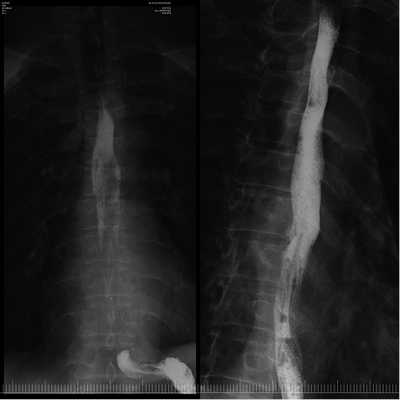

Образование извлечено с помощью эндоскопической петли и направлено на гистологическое исследование. На месте удаленного образования определялся дефект слизистой оболочки до 2 см в диаметре без визуальных признаков повреждения мышечного слоя стенки пищевода (рис. 5). В послеоперационном периоде пациенту рекомендована щадящая диета с исключением грубой пищи, проведена антисекреторная терапия ингибиторами протонного насоса. В 1-е сутки после операции ESD выполнено рентгенологическое контрастное исследование с целью исключения перфорации стенки пищевода с учетом первого опыта диссекции. Затекания контрастного вещества за контуры пищевода не отмечалось (рис. 6, 7).

Рис. 6. Контрастная рентгенограмма пищевода. Затекания контрастного вещества за контуры пищевода нет.

Рис. 7. Контрастная рентгенограмма пищевода. Затекания контрастного вещества за контуры пищевода нет.